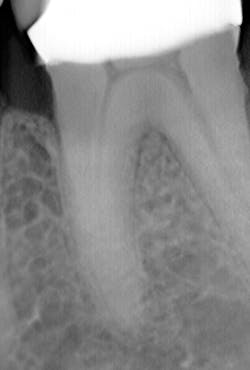

What’s unique about this system is that it uses nanotube technology to capture standard 2D images (figure 2) and gives you the option of taking a tomosynthesis image, which captures multiple images from several angles (figure 3). Images are compiled into a sliced volume and dissected into 0.5 mm or 0.1 mm slices that you can scroll through, rotate, enlarge, measure, and adjust. The system can “un-overlap” many teeth; this is convenient because with regular 2D x-rays, I had to retake the image at different angles and often with little success.

In fact, twice today I was able to see something with Portray that wasn’t visible in the original 2D x-ray (figure 6). I don’t always take 2D images now, but I do when I think the case is straightforward or the patient has very little dental history. I often end up taking a tomosynthesis image just to be safe. With the 3D image I can scroll from buccal to lingual through the tooth and get much more data (figure 7). The new system has replaced my 2D PAs and bitewings.

Fortunately, 3D intraoral tomosynthesis found its way into the dental field. Based on the findings from a study out of the University of North Carolina, dentists who use 3D tomosynthesis for intraoral x-rays can detect approximately 36% more caries (figures 8 and 9).1 That’s tremendous!